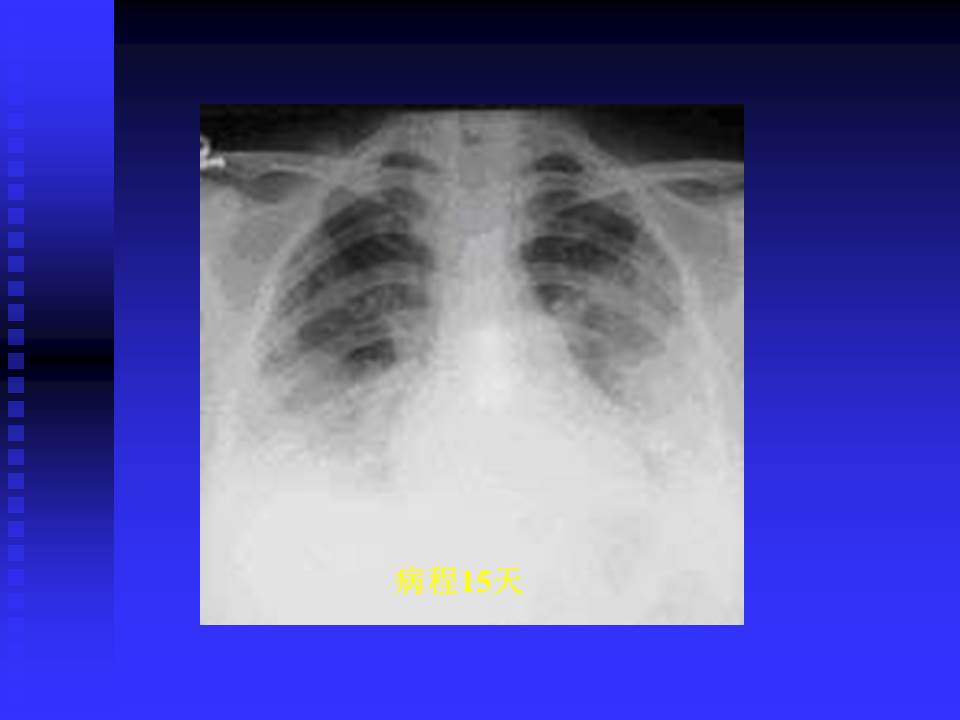

【PPT】严重急性呼吸综合征的影像鉴别诊断